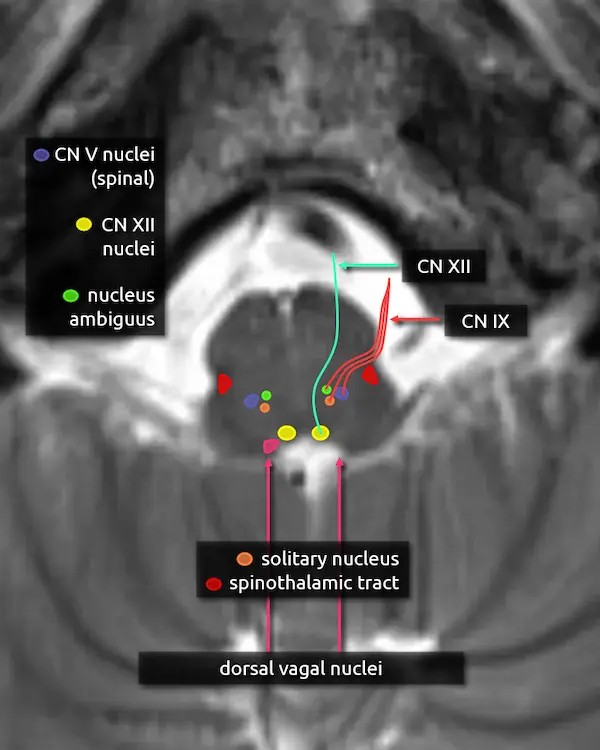

6. Hypoglossal nucleus (CN XII)

The hypoglossal nucleus is located in the dorsal medulla near the midline. It is elongated in the craniocaudal dimension, with extension towards the mid medulla approximately to the most inferior aspect of the fourth ventricle, called the obex. For imaging purposes, the obex is essentially the inferior tip of the median aperture. In reality, they are separate structures.

7. Hypoglossal nerve (CN XII)

The hypoglossal nerve travels anteriorly from the hypoglossal nucleus and exits the ventral medulla. From there, it traverses the premedullary cistern and enters the hypoglossal canal of the occipital bone. It innervates the muscles of the tongue besides the palatoglossus muscle, which is innervated by the vagus nerve (CN X).

Hypoglossal nerve palsy may cause weakness of the ipsilateral tongue musculature, eventually causing atrophy of the musculature which may be seen on imaging. On physical exam, the tongue may deviate towards the paralyzed side during protrusion.

8. Nucleus ambiguus

The nucleus ambiguus is located primarily in the upper medulla just dorsal to the inferior olivary nucleus. It is a motor nucleus that receives fibers from the corticobulbar tract and provides fibers to the glossopharyngeal nerve (CN IX), vagus nerve (CN X), and spinal accessory nerve (CN XI). It innervates muscles of the pharynx and larynx, primarily involved in swallowing and speech.

Lesions of the nucleus ambiguus may cause dysphagia and hoarseness.

9. Glossopharyngeal nerve (CN IX)

The glossopharyngeal nerve exits the lateral aspect of the upper medulla before coursing slightly inferiorly and entering the jugular foramen of the skull base. It has sensory, motor, and parasympathetic functions provided by four nuclei:

Sensory

a. Solitary nucleus: taste from posterior 1/3 of the tongue

b. Spinal nucleus of the trigeminal nerve: somatic sensation to the posterior 1/3 of the tongue, pharynx, middle, ear, and tonsils.

Motor

a. Nucleus ambiguus: stylopharyngeus muscle, responsible for elevation of the pharynx during speech and swallowing.

Parasympathetic

a. Inferior salivary nucleus (not pictured): small nucleus in the lower pons superomedial to the nucleus ambiguus. It innervates the parotid gland.

10. Dorsal vagal nuclei (CN X)

The dorsal vagal nuclei are elongated and located in the majority of the dorsal medulla posterolateral to the hypoglossal nucleus. It mainly provides parasympathetic innervation to several visceral organs in the chest and abdomen.

11. Vagus nerve (CN X)

The vagus nerve exits the lateral brainstem just below the glossopharyngeal nerve (CN IX) and follows a similar course. Four nuclei contribute to the nerve: the dorsal vagal nucleus, nucleus ambiguus, solitary nucleus, and spinal nucleus of the trigeminal nerve.